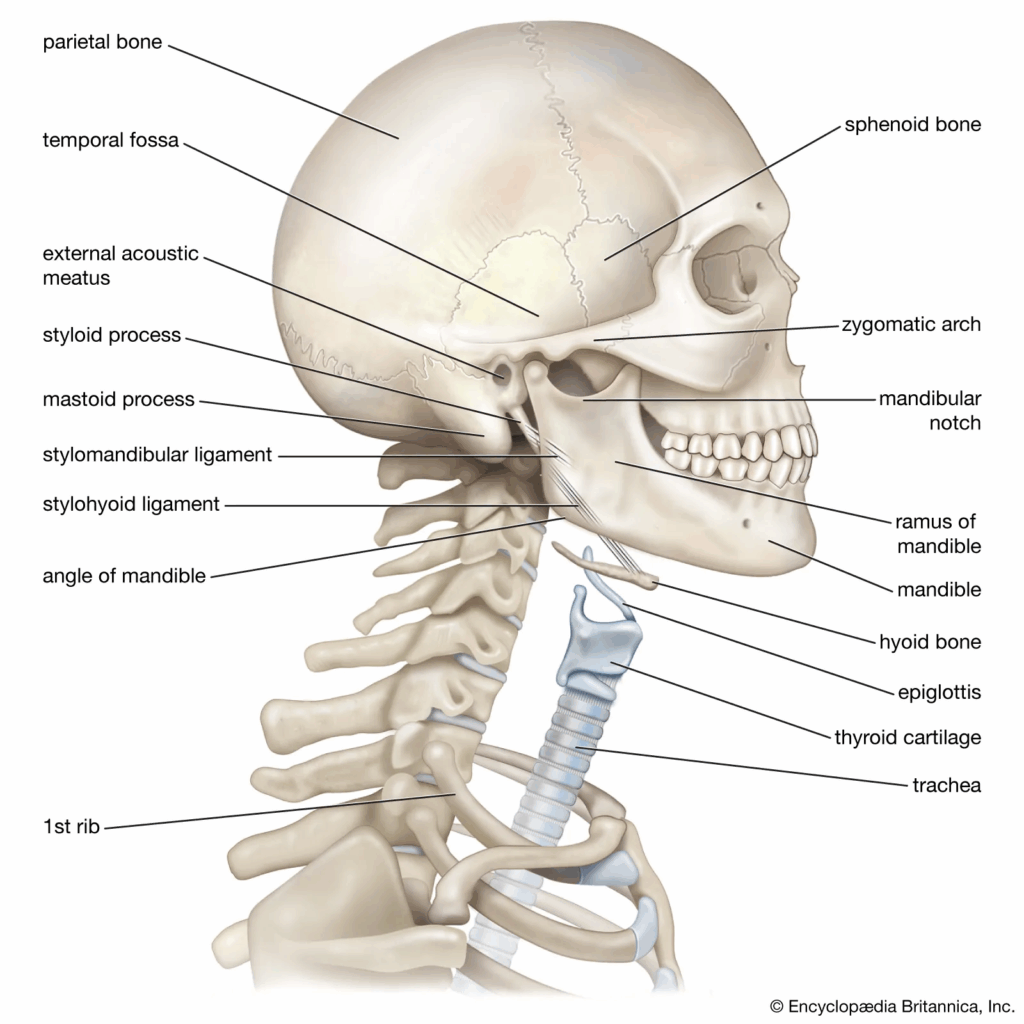

Doctors performed detailed imaging of the cervical spine and found a rare type of injury affecting two vertebrae. This kind of injury does not fit neatly into common medical classification systems, making it a unique case for medical professionals and researchers to study.

Doctors noted that this type of injury pattern is extremely uncommon. It highlighted how even a single falling object can cause serious harm and how important it is for medical teams to be aware of unusual injury presentations that may not match typical guidelines.

The incident also pointed to the need for ongoing review and improvement of classification systems used to understand and diagnose spinal injuries, ensuring that rare cases are better recognized in the future.